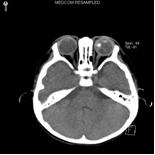

4.CT掃描檢查 CT檢查可顯示眼內及眼眶內的腫瘤病變,可見玻璃體腔內出現密度增高不均勻的局限性腫塊,常伴鈣化斑,晚期病例視神經增粗,視神經孔擴大。